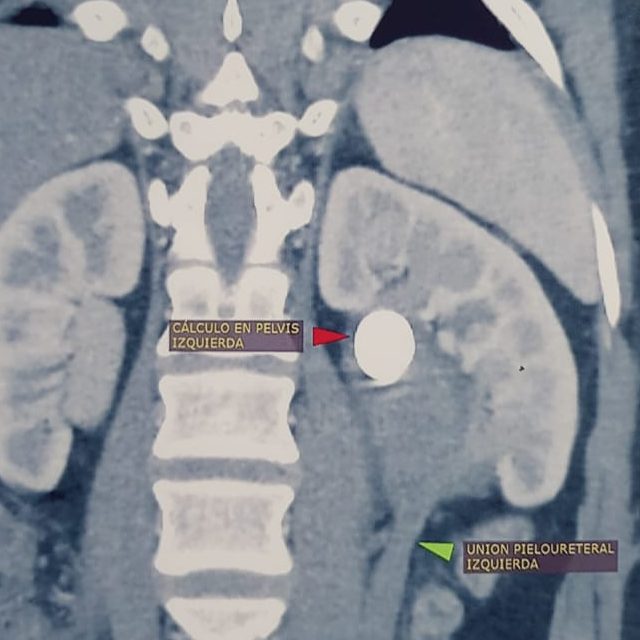

- Cálculos renales

- Cálculos ureterales

Sus principales investigaciones y publicaciones se centran en temas de cálculos renales.